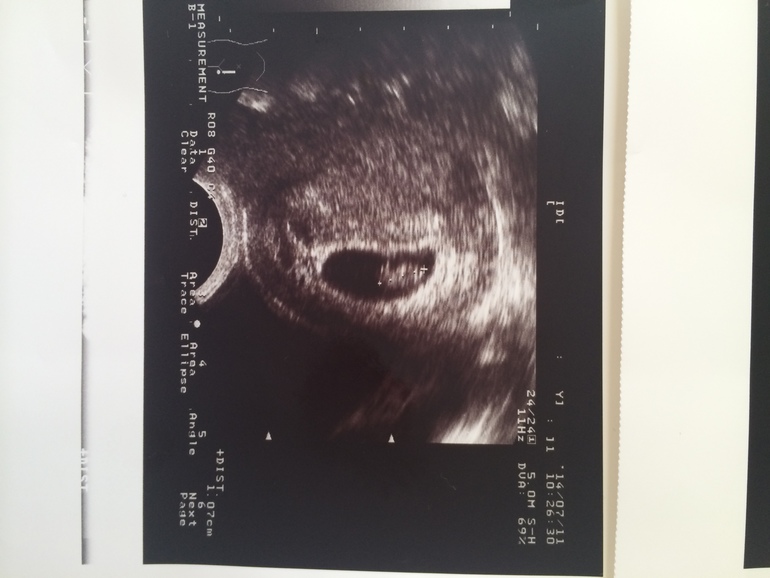

УЗИ показало, что срок 4 недели, но есть угроза и теперь я должна три дня минимум провести в постели с кучей лекарств. Конечно, я не выдержала и 2-х дней и снова пустилась в работу. А после работы мне вздумалось еще и круги по парку нарезать, гуляя пешком. И снова кровь и этот страх! И опять прием у гинеколога и УЗИ. Не повторяйте моих ошибок!!!

Сегодня настал день нашего третьего УЗИ, гинеколог назначила. Идет 9 эмбриональная и 11 акушерская недели. Конечно, у всех к этому времени только первое УЗИ случается, но у меня угроза и поэтому такой мониторинг. На УЗИ мы пошли вместе с будущим папой. Нам дали послушать биение сердца нашего малышика. Мы смогли хорошо его разглядеть. Он так смешно дергал ручками и ножками, танцевал джигу-дрыгу в моем животике))) Мужа это очень впечатлило, он еще пару раз за день потом это вспоминал и даже показывал, как он двигался! Не зря я его взяла с собой. Хотелось, чтобы наш ребенок перестал быть для него чем-то эфемерным, а перешел в разряд реального.

Итак, нам сказали, что ребенок растет и развивается очень хорошо и даже с опережением, у него длинные ноги и руки, будет высокий малыш, в папу. Угроза пока сохраняется, и я должна быть очень осторожна. Теперь меня отправили на постановку на учет, выбираю себе врача. И недели через 2 идем на 1 скрининг.

Ух, самое страшное позади, и я теперь так счастлива. Смотрю на снимок УЗИ, где уже очень хорошо все видно и понятно, и сердце заходится радостью! Я переполнена впечатлениями.